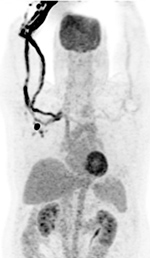

Brown fat or brown adipose tissue (BAT) and white adipose tissue are the two kinds of fat (adipose tissue) found in mammals. Brown fat is especially abundant in newborns with its primary function being to generate body heat. Brown fat cells contain many small droplets of lipids and a high number of mitochondria which make it brown. It contains more capillaries than white fat having a greater need for oxygen delivery. Brown fat becomes less common as one ages. It is still present in adults in the upper chest, neck, paraspinal, and suprarenal regions and is more metabolically active with cold exposure (figure 34).

63 year-old woman with right femoral hardware for 3 years presented with right leg pain. Whole body Tc-99m HMPAO tagged WBC (A) scan demonstrated focal abnormal activity in the distal right femur which may represent infection or focal marrow. Tc99m sulphur colloid bone marrow scan (B) four weeks later demonstrates similar focal uptake in the distal right femur confirming the etiology as uptake in displaced marrow and not infection. 60 year-old man with history of lung cancer and left hip arthroplasty suffered from stiffness in the left hip region. Axial CT, FDG PET, fused axial, and coronal PET-CT demonstrates increased uptake of FDG in heterotopic ossification in the musculature of the left thigh. 30 year-old woman with history of lymphoma. Axial CT, PET, PET-CT fused, and PET MIP images demonstrate intense FDG activity in the bilateral neck and paravertebral regions with a symmetrical distribution. Cross-sectional images clearly show that activity in the neck corresponds to fat and therefore consistent with brown fat activity. Brown fat activity is seen more commonly in younger patients and is also increased in response to hypothermia (so keep patients warm both pre and post injection of FDG).